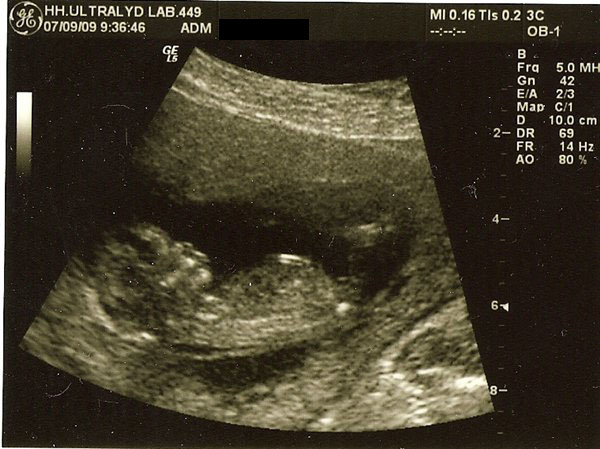

De første 2 billeder er fra nakkefoldescanningen (i uge 13), det næste er fra misdannelses scanningen i uge 20 og det sidste (og dårligeste) er fra den første hjerte scanning i uge 26.